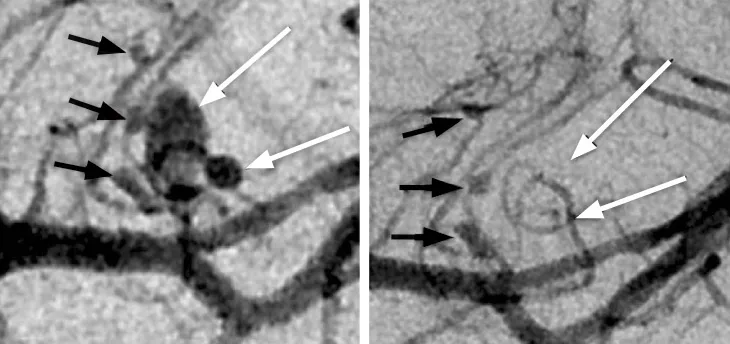

During shingles, the virus can also infect arteries. The immune system’s attempt to clear the infection from the vessels sparks inflammation, damaging artery walls. When this post-shingles complication, called varicella zoster virus vasculopathy, hits arteries in the brain, stroke risk goes up.

The reactivated virus may also be behind some cases of a painful inflammation of the arteries at the temples called giant cell arteritis. More common in older adults, the disorder causes severe headaches, jaw pain and vision problems, and can lead to blindness. Nagel and colleagues found the virus in 61 of 82 artery samples taken from the temples of patients with the disorder, the team reported in 2015 in Neurology.